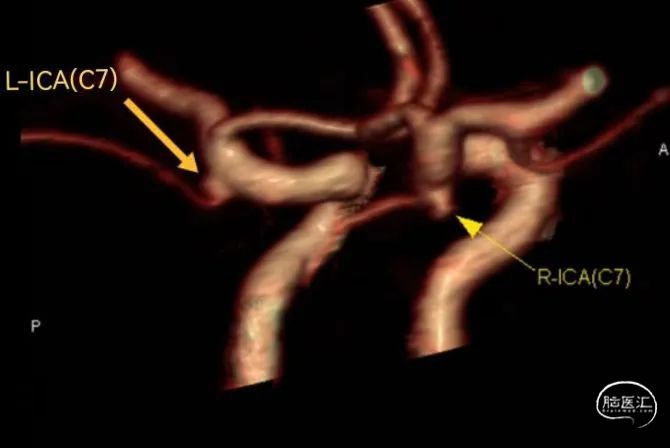

头颈CTA:

右侧颈内动脉交通段后缘(约后交通动脉开口左缘处)见小结节突起影,基底部宽约0.25cm,高度约0.2cm,提示动脉瘤可能性大。

左侧颈内动脉交通段后缘小突起影,基底部宽约0.2cm,高度约0.1cm,考虑动脉瘤可能。

术前诊断:双侧颈内动脉C7段微小动脉瘤(左侧责任) 。